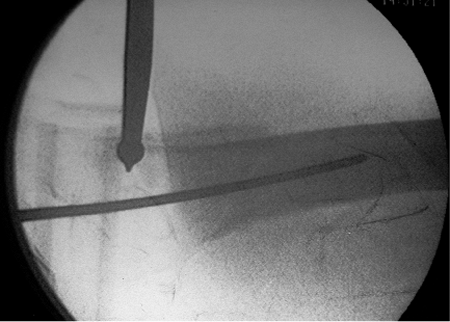

should be verified with bi-planar imaging. Using a freehand technique,

we insert a 3.2-mm guide pin percutaneously (Fig. 17.6),

about 3 to 4 cm proximal to the trochanter, engaging the bone at or

just medial to the tip of the greater trochanter. This location will

counteract the tendency toward varus and increased neck-shaft offset as

well as minimize any damage to the gluteus medius insertion (Fig. 17.7). Based on the lateral view, the guide pin should be centered in the canal (Fig. 17.8A), and based on the AP, it should be aimed slightly medial (Fig. 17.8B).

Figure 17.8. A. Ideal guide pin location on the AP view: centered in the intramedullary canal. B. Ideal guide pin location: centered on the lateral view.

|